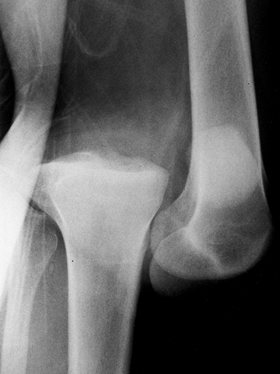

![]() |

Figure 91.3. Lateral radiograph of an anterior dislocation.